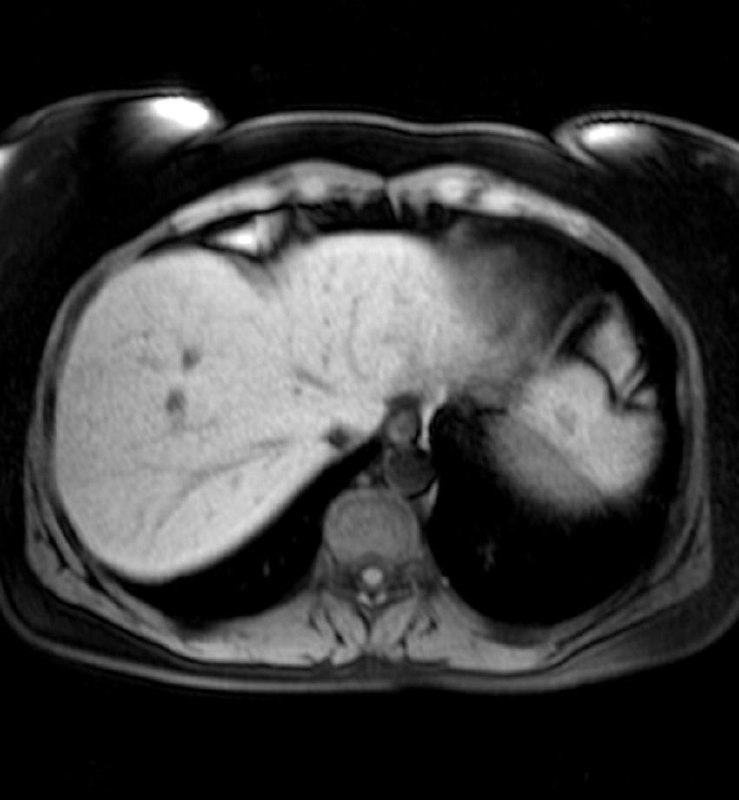

40 лет.

Думаю, что рак в хвосте панкреас, с вот такими метастазами в печень.

Ну, или и в панкреас тоже метастаз, хотя, других опухолей в животе не обнаруживается.